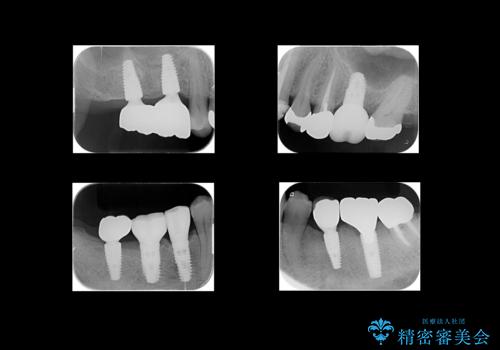

右上56および左下5は割れていたためやむなく抜歯しインプラントにしていきました。

左下7(一番奥の歯)は抜歯をせずに済みましたが、高さがないため上の歯を矯正治療で沈め、また、歯ぐきの手術を合わせて行いクラウン(被せ物)をしっかり入れる処置をおこなっています。

治療後は、歯が割れないようにナイトガードをお渡ししています。